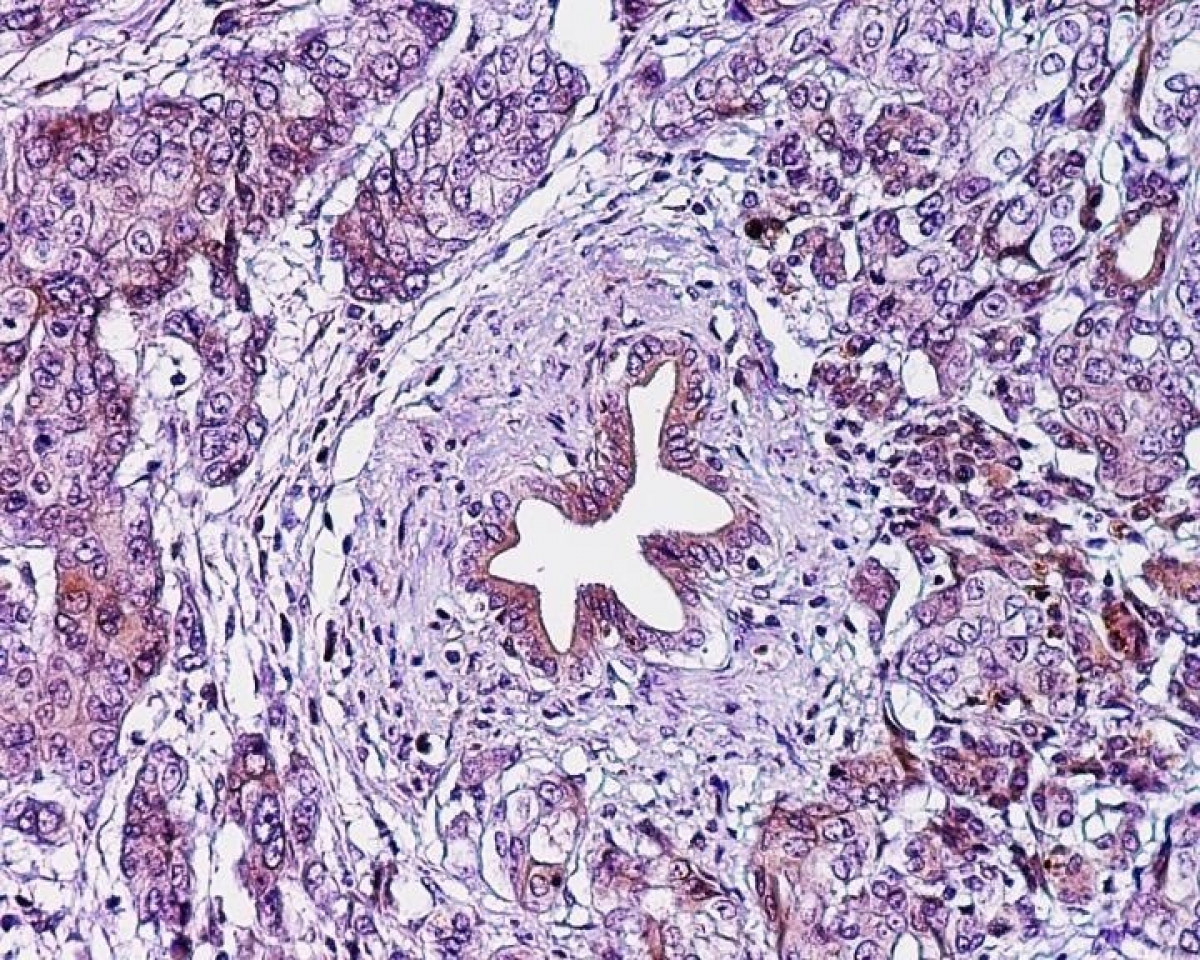

Dado que los TNE pueden tener su origen primario en muy diversas localizaciones del organismo, incluido un porcentaje del páncreas, cada paciente tiene un comportamiento muy diferente.

A esta circunstancia, que determina cómo se va a comportar el tumor y su pronóstico, hay que añadir también tanto la agresividad del cáncer según su grado de diferenciación histológica como si el tumor produce o no hormonas.